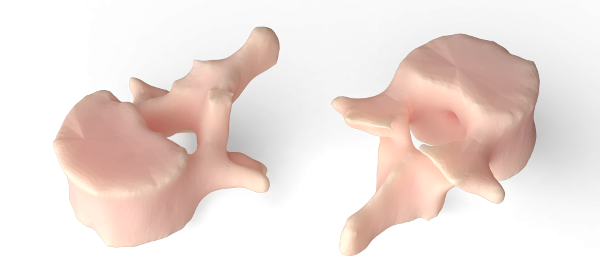

TRINOTA aims to help doctors assess patient specific treatment efficacy with the use of 3D visualization (Physical and Digital Models) of a patient's region of interest (ROI).

With the use of our Ultra High Resolution Professional Grade 3D Printer, we can produce physical models of the patient's ROI.